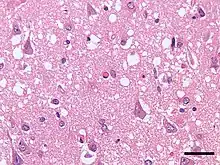

Micrograph showing spongiform degeneration (vacuoles that appear as holes in tissue sections) in the cerebral cortex of a patient who had died of a prion disease (Creutzfeldt-Jakob disease). H&E stain. Scale bar = 30 microns (0.03 mm).

Prions cause neurodegenerative disease by aggregating extracellularly within the central nervous system to form plaques known as amyloids, which disrupt the normal tissue structure. This disruption is characterized by "holes" in the tissue with resultant spongy architecture due to the vacuole formation in the neurons.[68] Other histological changes include astrogliosis and the absence of an inflammatory reaction.[69] While the incubation period for prion diseases is relatively long (5 to 20 years), once symptoms appear the disease progresses rapidly, leading to brain damage and death.[70] Neurodegenerative symptoms can include convulsions, dementia, ataxia (balance and coordination dysfunction), and behavioural or personality changes.